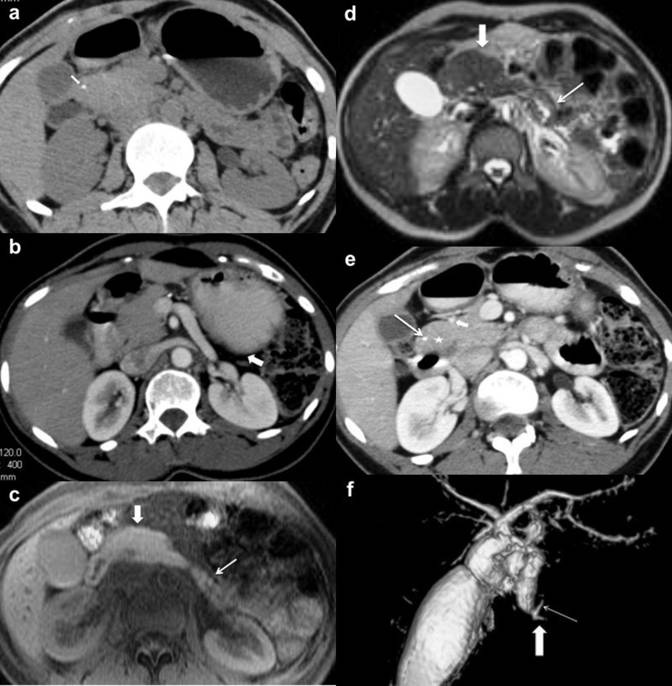

A 35-year-old lady presented with nausea and intermittent pain in epigastric region. She had two such episodes of pain within a period of one year prior to presentation. During the above episodes her serum amylase and lipase levels were within normal limits. On investigation her fasting blood sugar level was normal, though she had impaired glucose tolerance test. She had no history of hepatobiliary disease or viral illness in childhood. Her initial ultrasonography examination at another institution was reported as normal. Ultrasonography examination at our institution revealed enlarged head with absence of body and tail. CT and MRI examination of pancreas showed absence of pancreatic body and tail, and the distal pancreatic bed was occupied by stomach, bowel loops along with small amount of fatty tissue (Figure 3ab). The pancreatic head was enlarged in size and showing two discrete lobulations at lateral contour on inferior aspect (Figure 3cde). Of the two lobules at head, one was oriented anteriorly (type I) and another lobule was oriented posteriorly (type II) in relation to superior pancreaticoduodenal artery (Figure 3c). The anteriorly and posteriorly oriented lobules were measuring 13 mm and 19 mm, respectively. The superior part of head was located medial and posterior to caudate lobe of liver. No focal calcification in pancreatic head was seen. She had fatty infiltration of liver and replaced right hepatic artery originating from superior mesenteric artery. The gastroduodenal artery was originating from replaced right hepatic artery. MRI and MRCP study confirmed absence of pancreatic body, tail as well as the dorsal duct. The ventral duct was present and it was not dilated (Figure 3f). Her epigastric pain was subsided following treatment with analgesics, proton pump inhibitor and pancreatic enzyme supplement.

Figure 3. Case #3. Thick slab maximum intensity projection coronal CECT image depicting stomach (thick arrow) abutting splenic vein (thin arrow). b. Axial T2W fast spin echo MR image depicts pancreatic head (thick arrow), splenic vein (short arrow), bowel loops in distal pancreatic bed (asterisk). c. CECT axial image depicts anterior lobulation (asterisk) and posterior lobulation of the head (thick arrow), anterior superior pancreaticoduodenal artery (short arrow). d. Axial fat saturated T1W spoiled gradient MR image depicts pancreatic head lobulations. e. Axial fast spin echo T2W MR image depicts pancreatic head lobulations. f. MRCP maximum intensity projection depicts short ventral duct (thick arrow) and common bile duct (thin arrow). No dorsal duct was seen. |